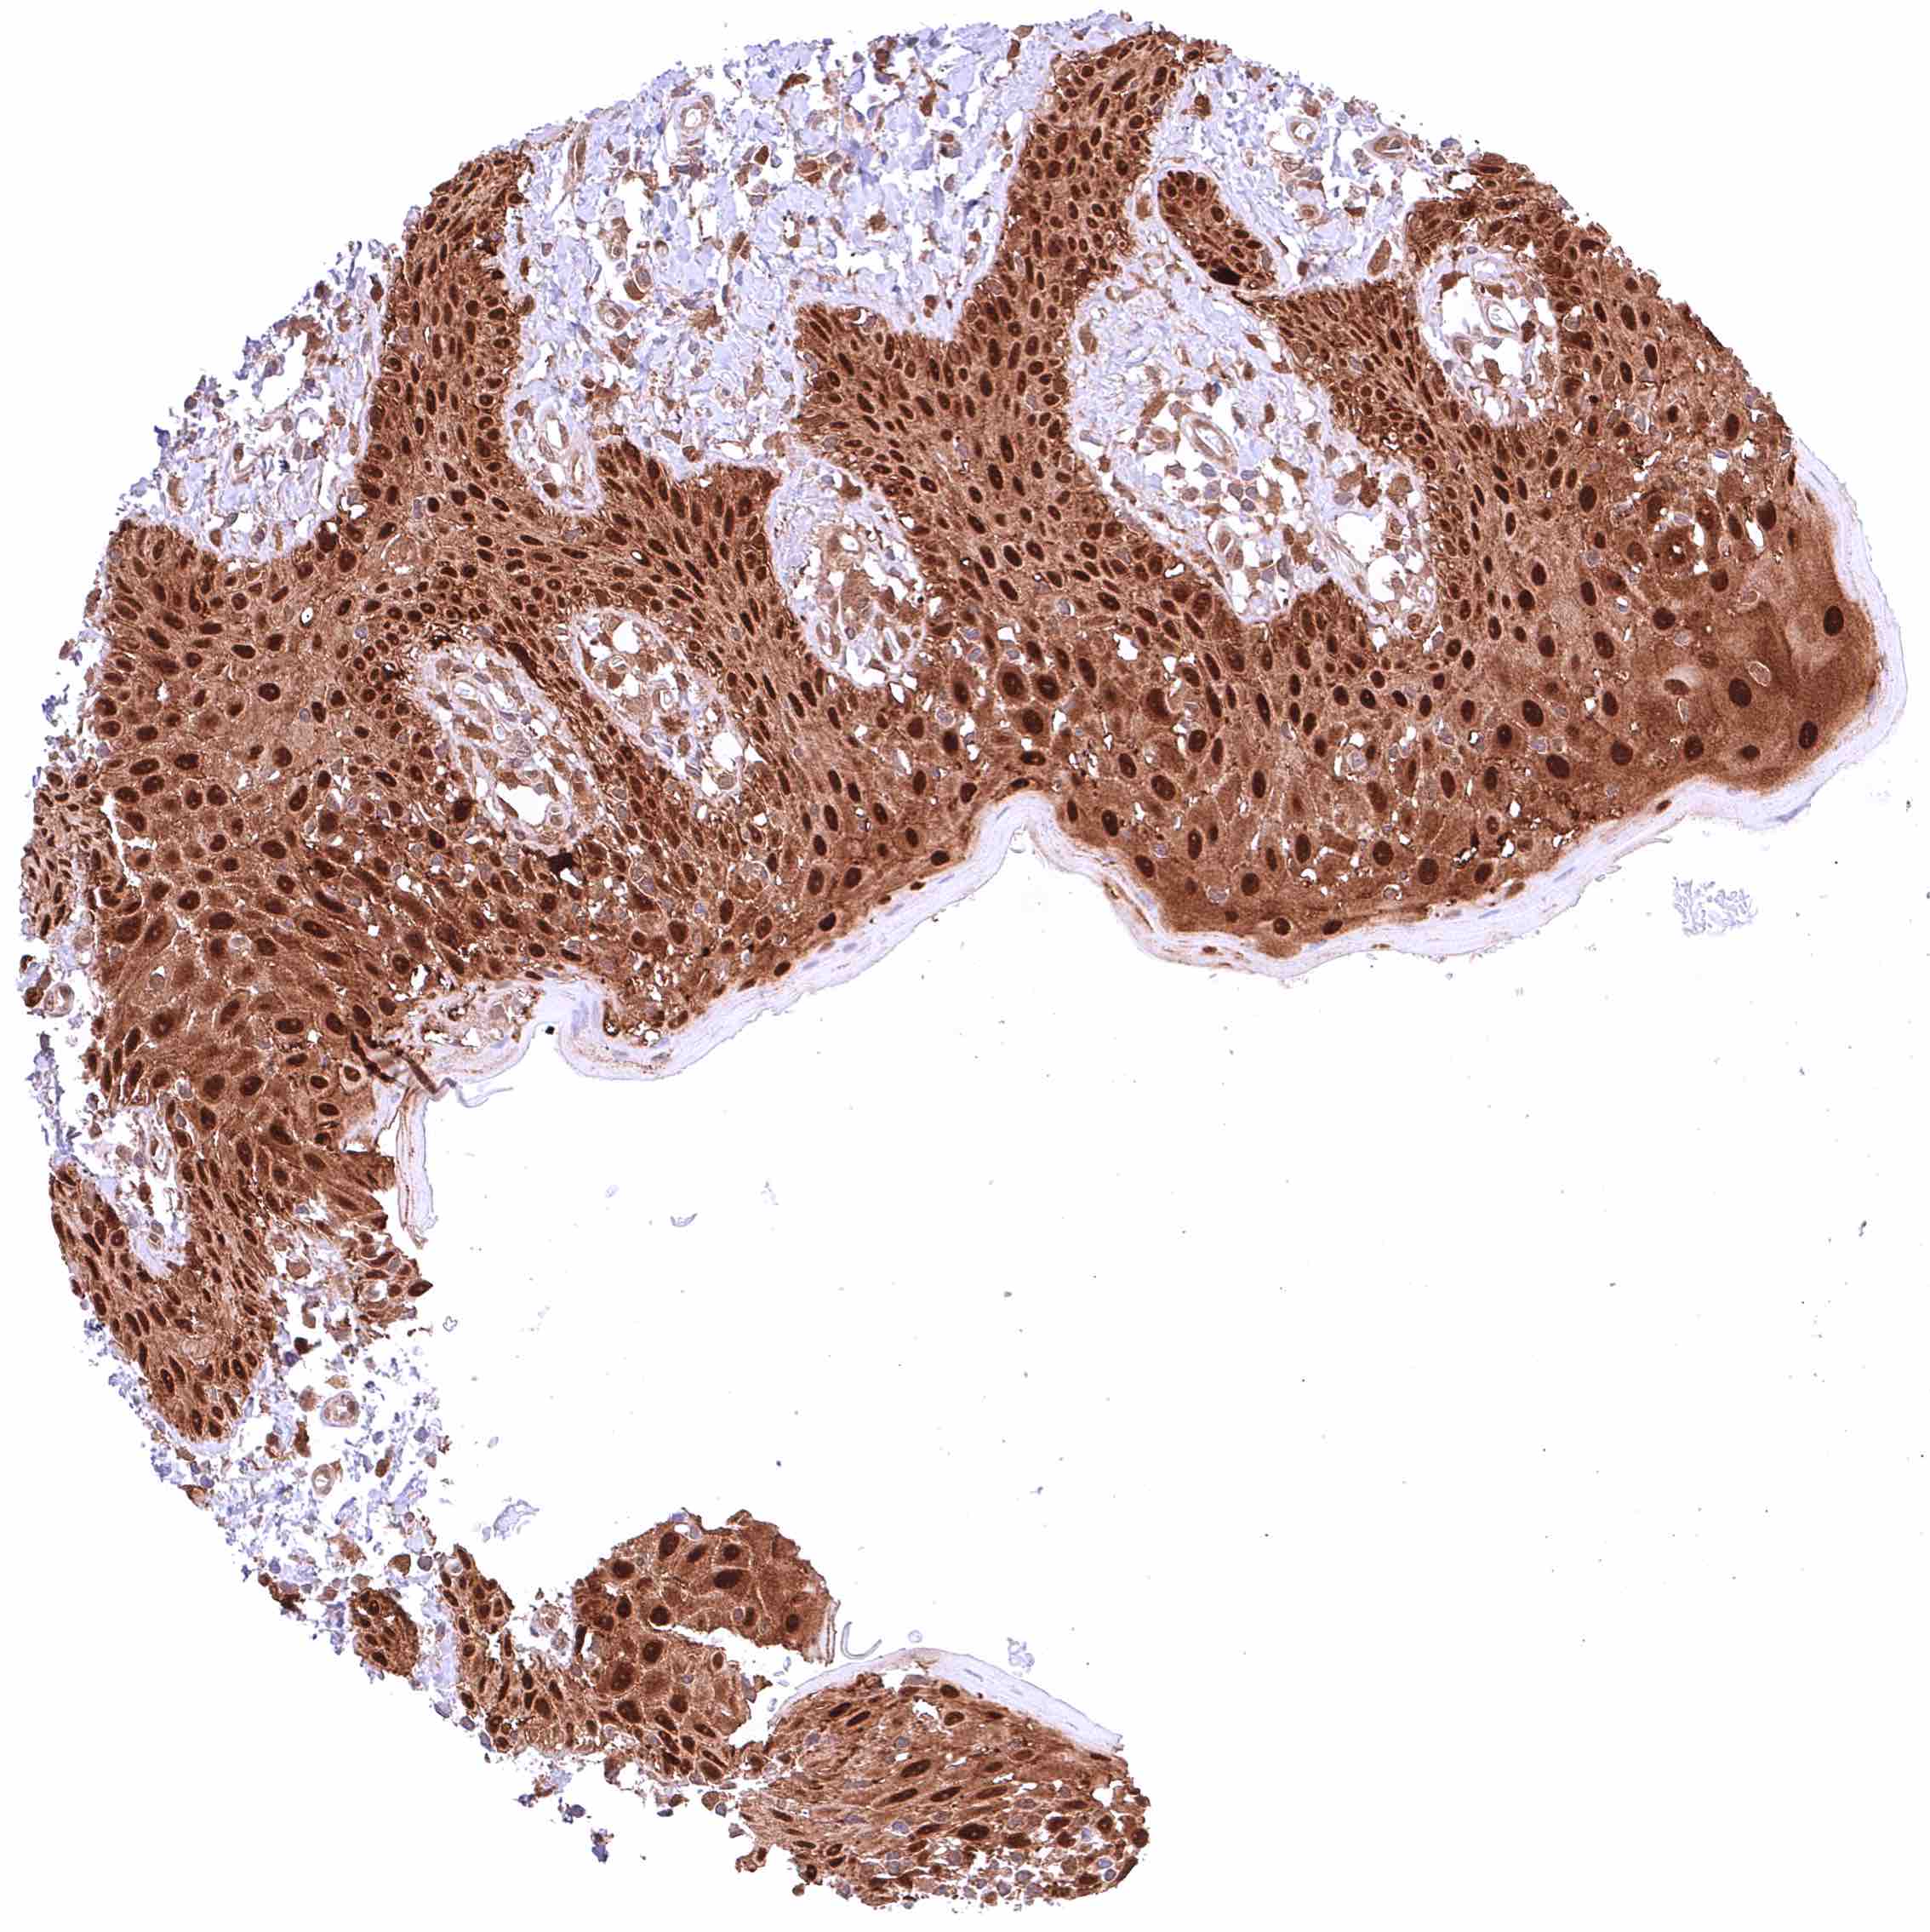

Skin – Strong nuclear and cytoplasmic GSTP1 positivity of all squamous epithelial cells.

Skin, ekkrine glands – Strong GSTP1 positivity of eccrine glands.

Skin, hairfollicle and sebaceous glands – Strong GSTP1 positivity of hair follicles and peripheral germinative cells of sebaceous glands while sebaceous cells remain GSTP1 negative.